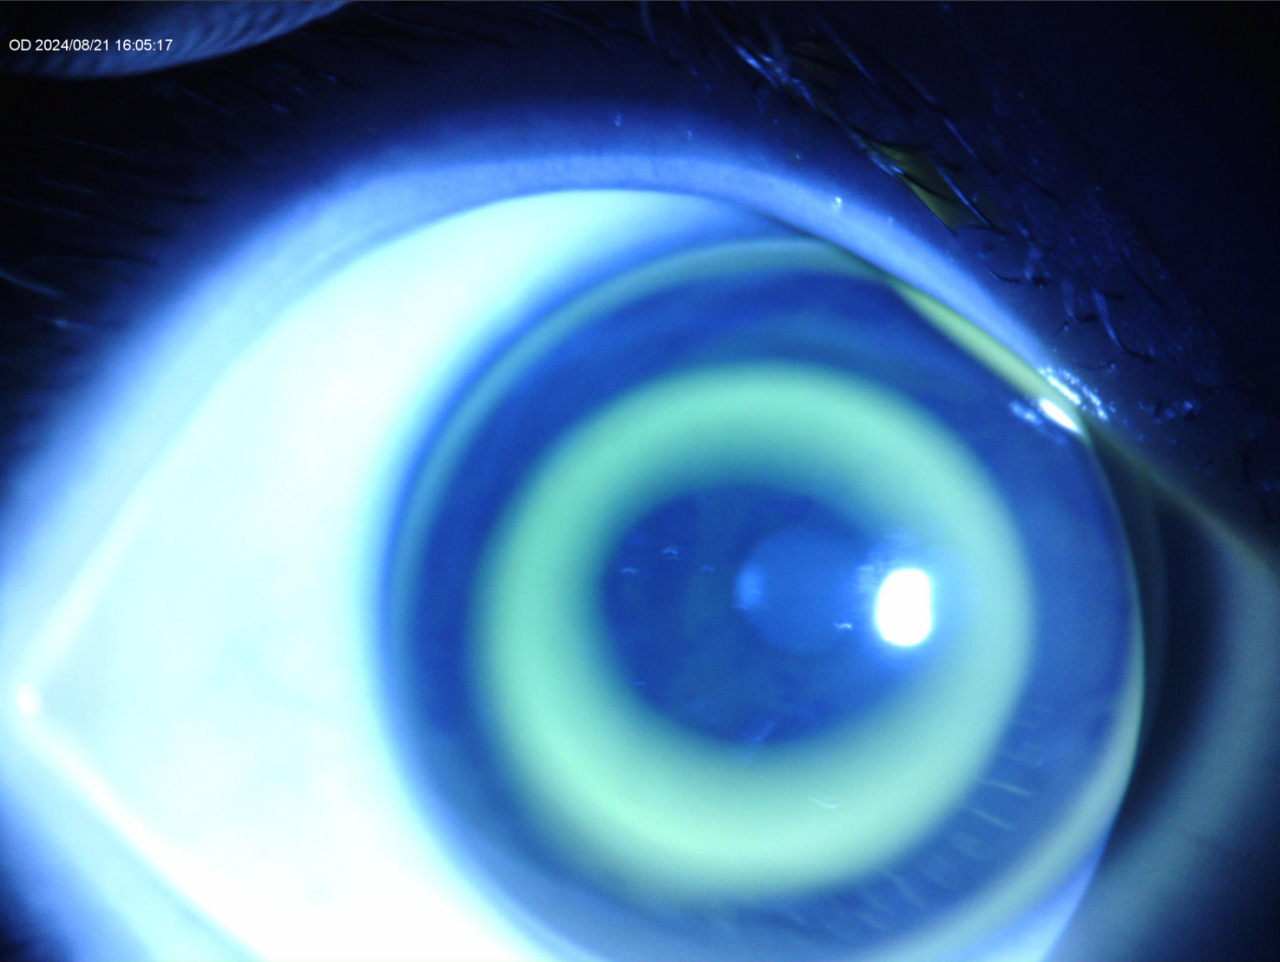

童享试戴荧光图及地形图(20分钟)

OD

OD:活动度良好,镜片直径适中,镜片定位居中,BC区略小,RC稍宽

OD:镜片定位居中,活动度良好,镜片直径适中,BC、RC边界略欠清,BC、RC弧段宽度适宜,AC无漏液,PC为均匀亮环。